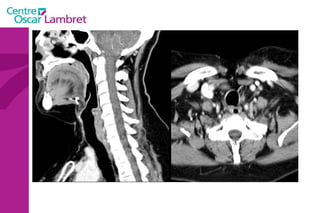

Le  Pharynx  : Carrefour aéro-digestif qui fait communiquer :  la voie aérienne avec le larynx (extrémité supérieure de la trachée).  la voie digestive avec l’oesophage. Il s’étend verticalement au-devant de la colonne cervicale, en arrière des fosses nasales (rhino-pharynx), de la cavité buccale (oropharynx) et du larynx (laryngo-pharynx).  Il est complètement tapissé par une muqueuse.  L’appareil respiratoire :

Fosses nasales Rhinopharynx Cavité buccale Oropharynx Hypo pharynx Larynx Œsophage trachée